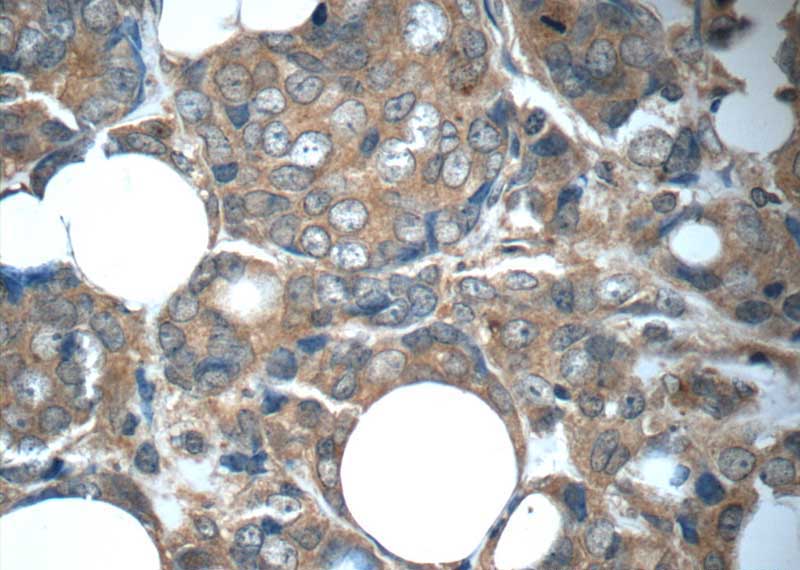

FGFR1 Mouse Monoclonal Antibody

FGFR1 Antibody 60325 1 Ig Proteintech